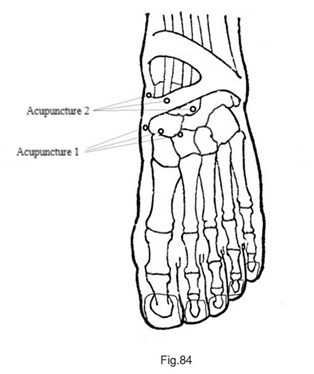

En suivant la technique 3C (Fig.30), on a localisé la zone correspondante au scaphoïde du pied gauche. Trois aiguilles ont été insérées autour de cette zone (Fig.83), ce qui a immédiatement atténué la douleur ; cependant, 10 minutes plus tard, la douleur persistait. Trois autres aiguilles ont été ajoutées près de l'articulation de la cheville (Fig.84) ; 10 minutes plus tard, la douleur au scaphoïde carpien avait disparu, mais une douleur était apparue au niveau du poignet. Lorsque le patient étendait son poignet et exerçait une pression, il ressentait une douleur au dos et à la paume du poignet.